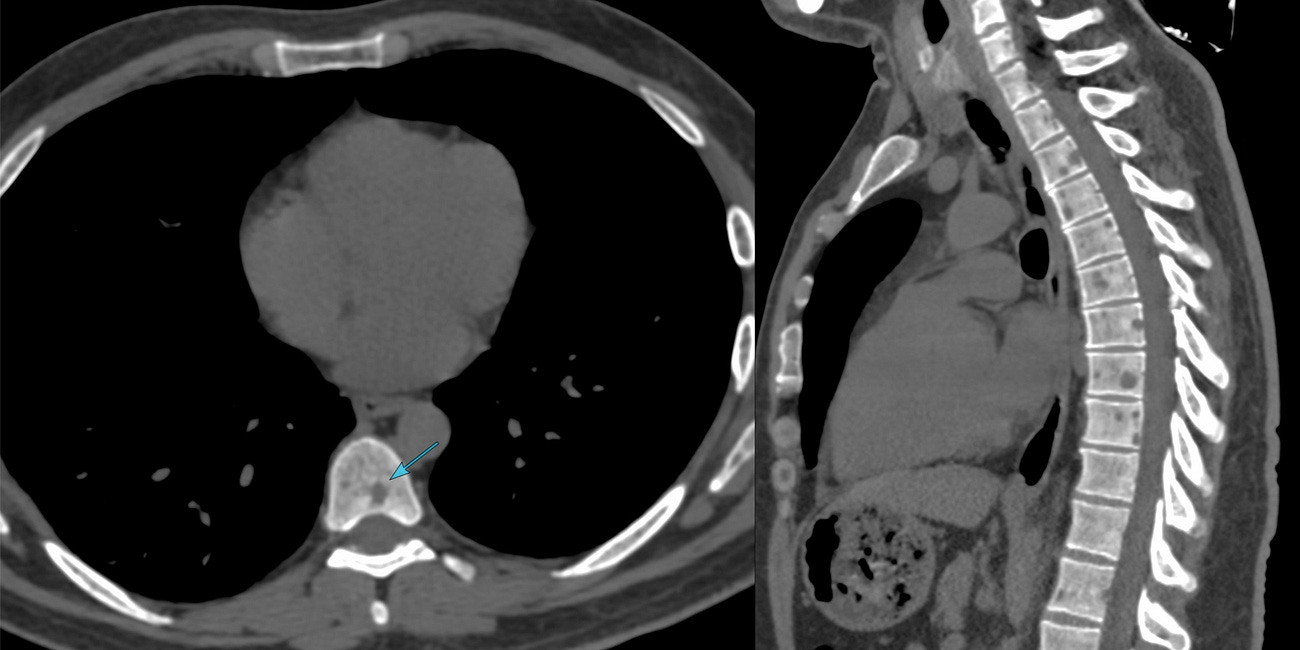

Case 55: Typical or Atypical?

A 70-years old presented with a slowly growing mass in the right thigh.